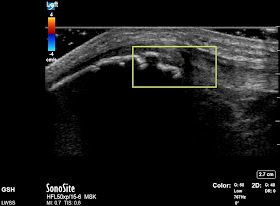

In our clinic at Lake Washington Sports & Spine, Dr. Hyman and I like to use high-resolution musculoskeletal ultrasound to image the patellar ligament complex. Ultrasound is a particularly great imaging tool for assessing tendons, for the following reasons:

1. It has the highest spatial resolution- 5-10 times higher than MRI

2. Real time assessment- it is the only imaging test that adds in actually touching the patient, so we can confirm that the area being imaged is actually painful. This is particularly valuable in rough-and-tumble athletes with a history of prior injuries, to help clarify whether the injury is new

3. Fantastic tissue differential- ultrasound is great at distinguishing between different tissue types

To give an example of an ultrasound image of a patellar-ligament complex injury, the image below is that of Sinding Larsen Johannson syndrome in an 11 year-old elite-level soccer player. The yellow box shows irregularity in the apophysis of the inferior pole of the patella (to help with orientation, left is superior, right is inferior)